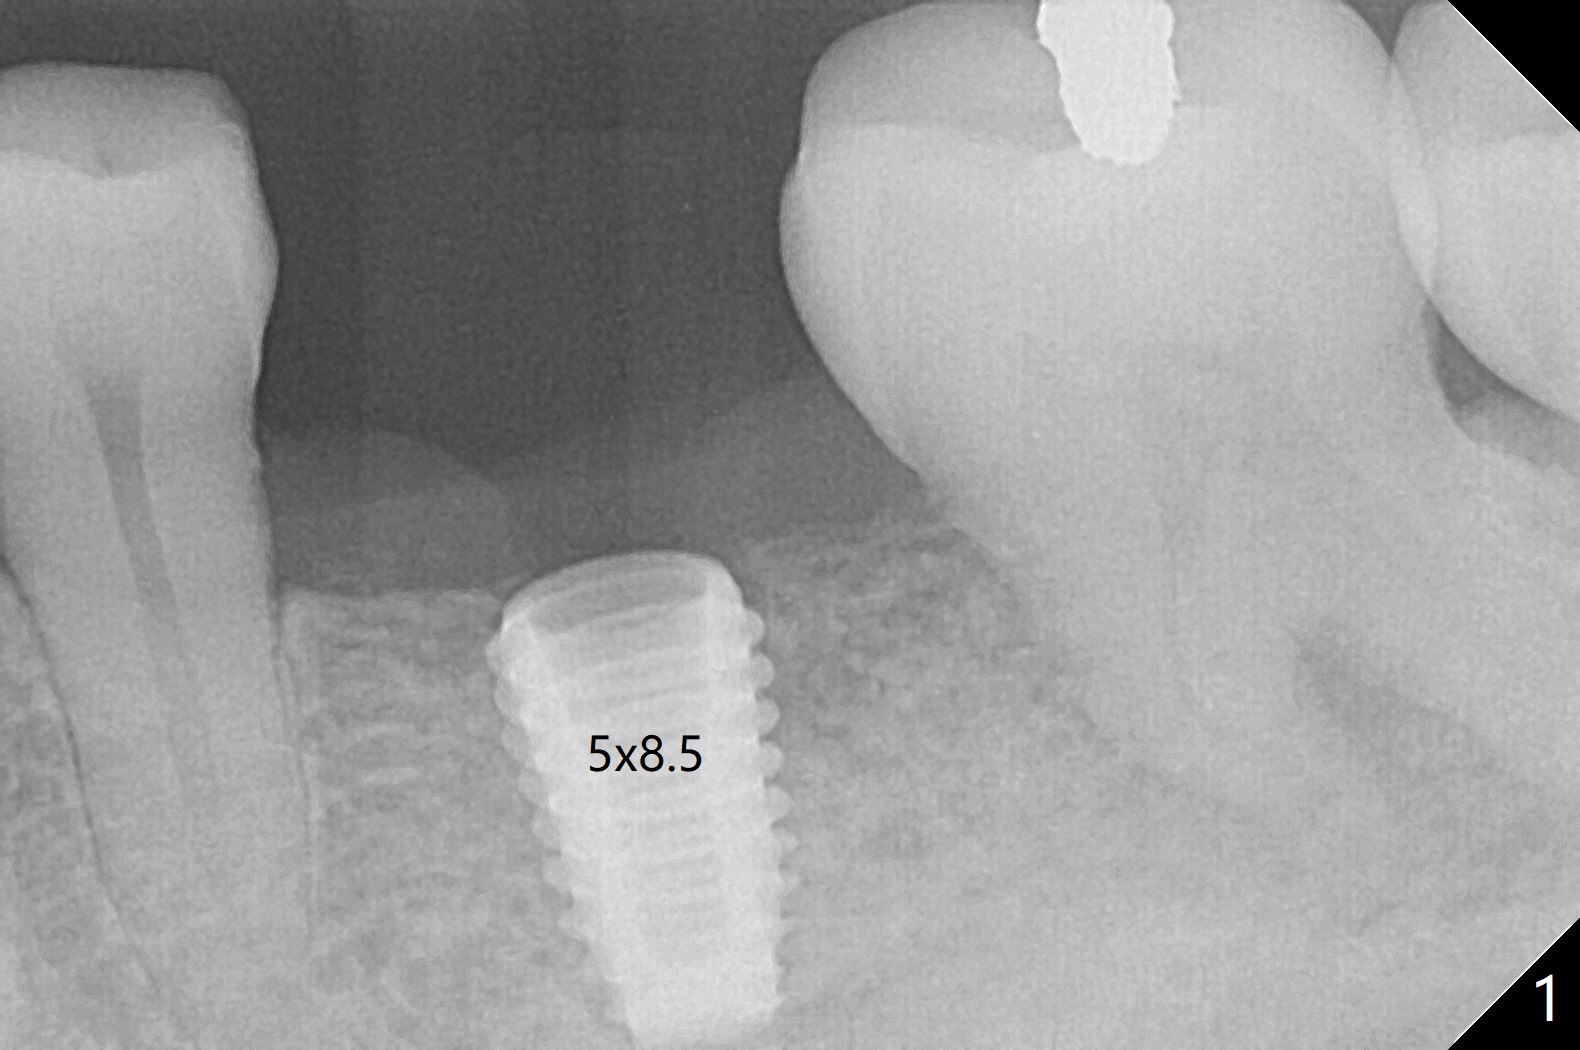

After use of 4.5x8.5 mm guide drill at #19, a 5x8.5 mm implant is placed with guide in place. When the latter is removed, the implant is found to be placed shallow. Following use of 4.5x10 mm drill for ~.75 mm deeper, the implant returns with deeper placement (Fig.1,2), confirmed after guide removal. The implant is further torqued 3 more times with visual confirmation of implant deeper placement. After seating a 5.5x5(3) mm healing abutment, autogenous bone graft is placed between the gingiva and the abutment to reduce chance of periimplantitis. The patient reports more severe pain (bone burn?) than free-hand placement at #30. In fact there is no bone loss around the implant 10.5 months postop (Fig.3).